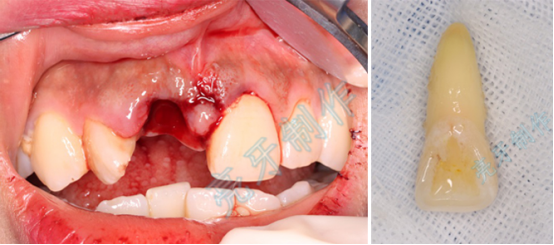

病例二:外伤导致上牙槽骨骨折,而且上下两颗门牙脱位;通过治疗,上下两颗门牙均恢复原来位置,而且和之前一样结实。